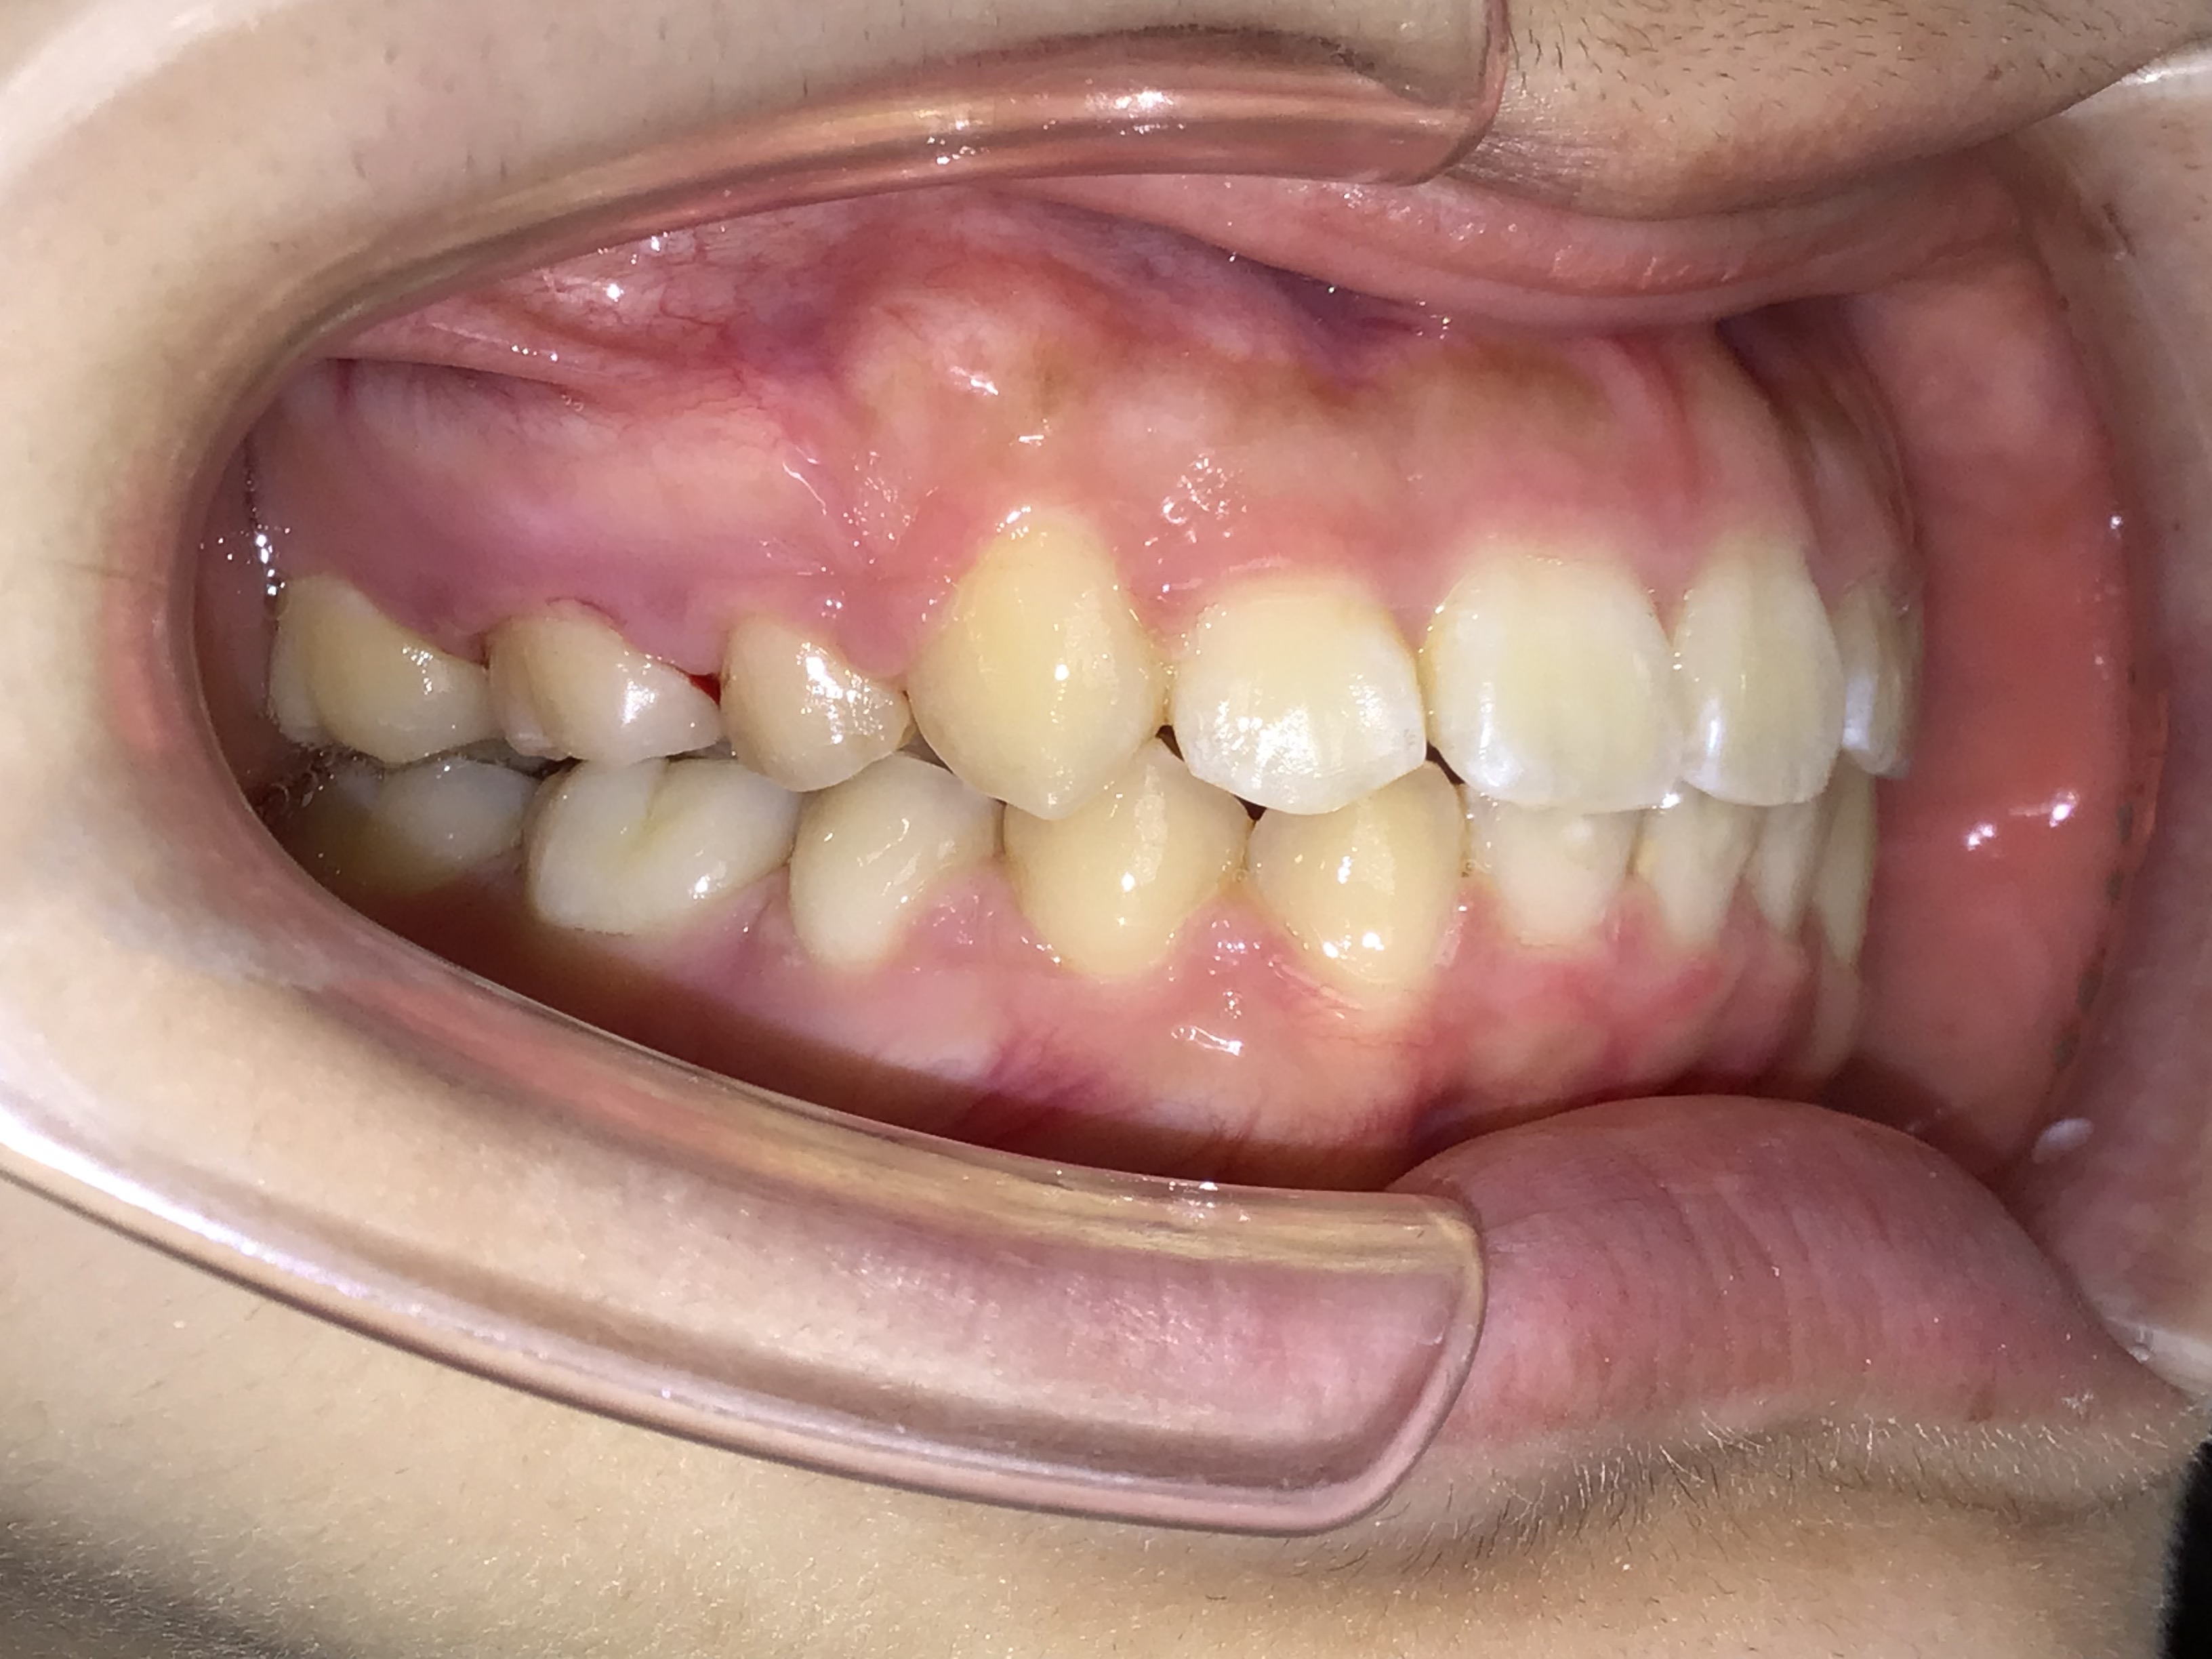

治療前 治療後 | 主訴 | 上の歯が出ている |

| 診断 | 叢生を伴う上顎前突症 |

| 初診時年齢 | 7歳10ヶ月 |

| 治療種別 | 1次矯正、2次矯正 |

| 外科処置 | 上顎左右第一小臼歯の抜歯 |

| 主な治療装置 | 歯列弓拡大装置、マルチブラケット装置など |

| 治療期間 | 1次矯正11ヶ月、2次矯正2年1ヶ月 |

| 治療費 | 1次矯正40万円(税別)、2次矯正50万円(税別) |

| リスク・副作用 | 矯正装置による不快感や痛みが生じることがあります(数日〜1、2週間で慣れることが多いです)。歯の動き方には個人差があり、予想された治療期間が延長する可能性があります。歯を動かすことにより歯根が吸収して短くなることや、歯ぐきがやせて下がることがあります。治療中は装置が付いているため歯が磨きにくくなり、むし歯や歯周病のリスクが高まります。治療途中に金属等のアレルギー症状が出ることがあります。顎関節症状(音が鳴る、あごが痛い、口が開けにくい)が出ることがあります。装置を外す時にエナメル質に微小な亀裂が入る可能性があります。装置が外れた後、保定装置を指示通り使用しないと後戻りが生じる可能性があります。 |